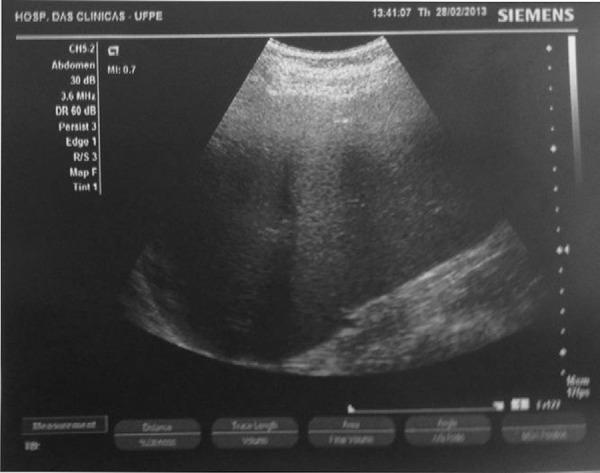

Fifty-five adults with hepatosplenic schistosomiasis and 30 healthy subjects were selected through a history of contact with contaminated water, physical examination and ultrasound characteristics such as periportal fibrosis and splenomegaly in the Gastroenterology Service of the Universidade Federal de Pernambuco. Blood samples were collected to determine liver function, blood counts, prothrombin (international normalized ratio), partial thromboplastin time and fibrinogen and D-Dimer levels using the Pentra 120 hematological analyzer (HORIBA/ABX), Density Plus (test photo-optical Trinity Biotech, Ireland) and COBAS analyzer 6000 (Roche). Furthermore, the longitudinal size of the spleen was measured by ultrasound (Acuson X analyzer 150, Siemens). The Student t-test, the Fisher test and Pearson's correlation were used to analyze the results with statistical significance being set for a p-value < 0.05.

通过接触受污染水的病史、体格检查以及伯南布哥联邦大学胃肠病科的门静脉周围纤维化和脾肿大等超声特征,选取了55例肝脾型血吸虫病成人患者和30名健康受试者。采集血样,使用Pentra 120血液分析仪(堀场/ABX)、Density Plus(爱尔兰Trinity Biotech公司的光电检测法)和COBAS 6000分析仪(罗氏)测定肝功能、血细胞计数、凝血酶原(国际标准化比值)、活化部分凝血活酶时间和纤维蛋白原以及D - 二聚体水平。此外,通过超声(西门子Acuson X 分析仪150)测量脾脏的纵向大小。采用Student t检验、Fisher检验和Pearson相关性分析结果,并将p值<0.05设定为具有统计学意义。